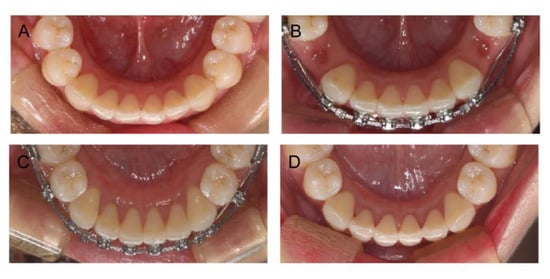

2.4. Treatment Progress